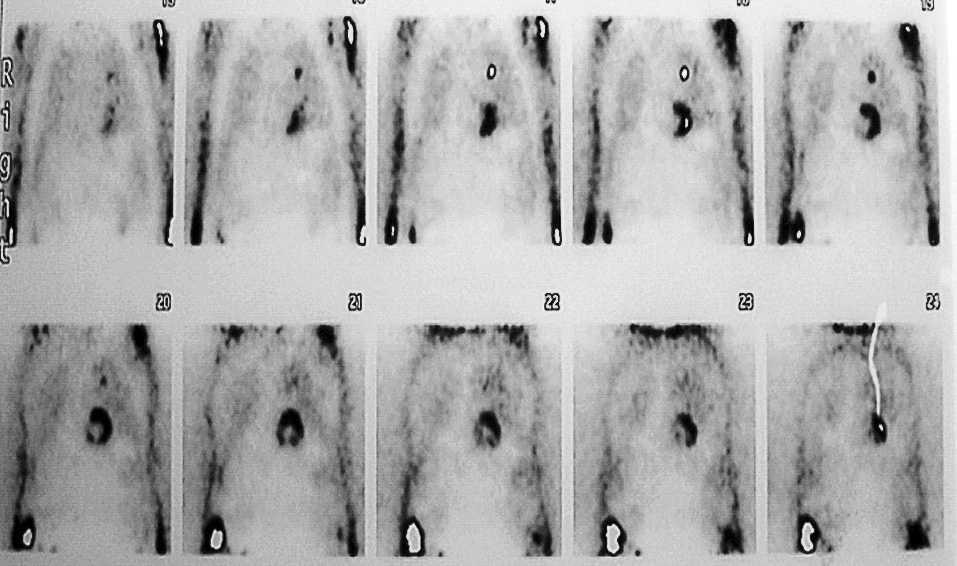

En la broncoscopia realizada se observaron signos de bronquitis crónica sin tumor intraluminal, con un aspirado y biopsia bronquial sin células neoplásicas. Se le realizó una PET con 18 fluorodesoxiglucosa (18-FDG), en la que destacaba un foco de hipercaptación único coincidente con la lesión conocida en el LSI (fig. 2).

Fig. 2. Tomografía por emisión de positrones con 18-FDG que muestra nódulo pulmonar hipercaptante en lóbulo superior izquierdo.